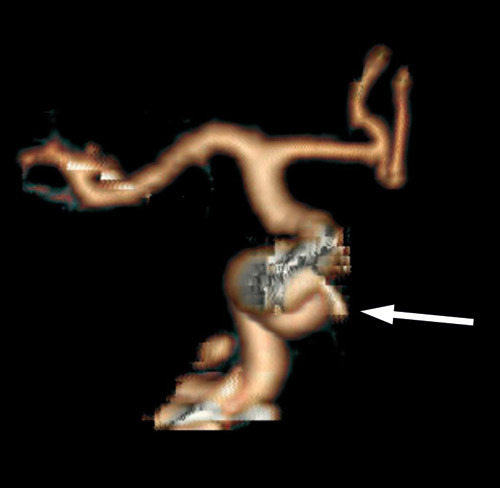

Cerebral CT og CT-angiografi like etter innleggelsen viste ikke tegn til blødning, men man fant på høyre side et intrakavernøst carotisaneurisme med diameter på 10 mm og en beineroderende prosess i sfenoidalsinus og clivus (fig 1, fig 2). MR-undersøkelse av hodet med og uten kontrast bekreftet et aneurisme i mediale del av sinus cavernosus på høyre side og beindestruksjon i samme område (fig 3).

Dagen etter transsfenoidal prøvetaking i narkose fikk pasienten akutt forverring av hodepinen, og det ble tatt en ny cerebral CT og CT-angiografi (fig 4). Den viste at den patologiske prosessen i sfenoidalsinus hadde ekspandert og at aneurismet hadde økt i størrelse til 16 mm i diameter.

Arteriell cerebral angiografi med kontrastinjeksjon på venstre side og kompresjon av a. carotis interna på høyre side viste at det ikke var overgang av blod fra venstre carotis til høyre hjernehalvdel via a. communicans anterior. Pasienten ville derfor ikke tåle okklusjon av a. carotis interna på den aktuelle høyre siden. Transkranial doppler bekreftet disse funnene. Videre viste arteriell angiografi at aneurismet var blitt dobbelt så stort på tre døgn (fig 5).